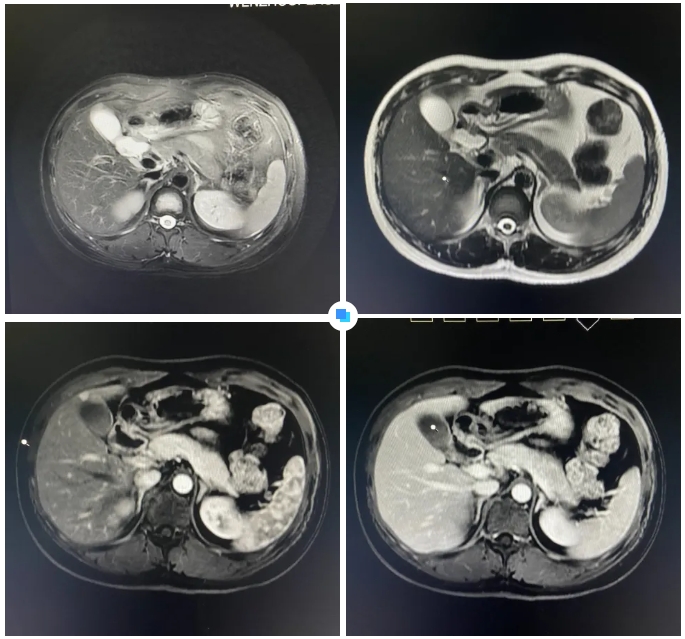

在被問到如何發(fā)現(xiàn)隱藏如此深的病灶時,和平國際醫(yī)院影像中心執(zhí)行主任侯文杰講到,該病灶在平掃T1、T2項(xiàng)都非常不清楚,只有彌散加權(quán)的情況下,病灶區(qū)域顯示出輕微的高信號,這一細(xì)微線索引起了他的高度關(guān)注。

隨后的增強(qiáng)核磁掃描發(fā)現(xiàn),在動脈期病灶顯著強(qiáng)化,而在門脈期明顯減退,這一特征與微小肝癌的表現(xiàn)高度吻合。